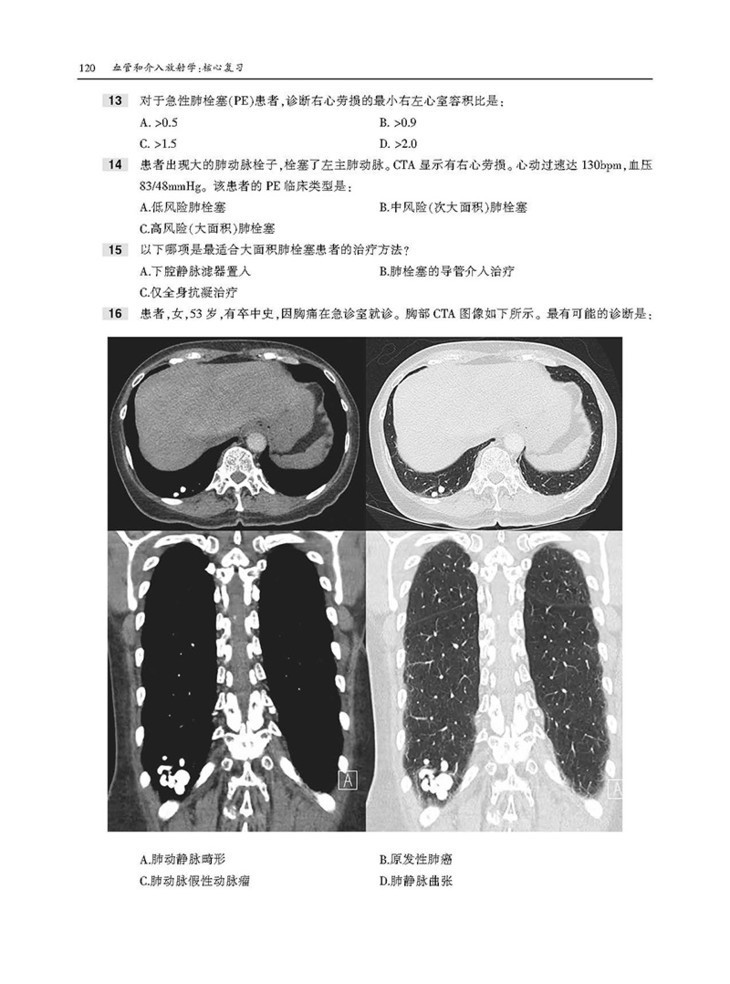

本书为“影像学核心复习系列丛书”之一,内容翔实,通过相关病例以及对应影像图,对血管介入放射学的内容进行了描述。本书囊括上百幅高清图像,直观展示病变要点。每章采取选择题形式,首先给出患者病史和影像图片,然后列出问题和选项,便于读者独立思考,选择答案。各章“答案与解析”部分不仅详细解释正确答案,而且说明错误选项的原因,此外,问题后还配有相关参考文献,有助于读者进一步扩展知识,有针对性地进行阅读和复习。

2. 直观性,本书按部位分别论述了胸部、胃肠道系统、泌尿系统、生殖内分泌系统的介入治疗,含百余幅高清图像,直观展示病变要点,是临床医师迫切需要并且手头缺乏的重要参考资料。